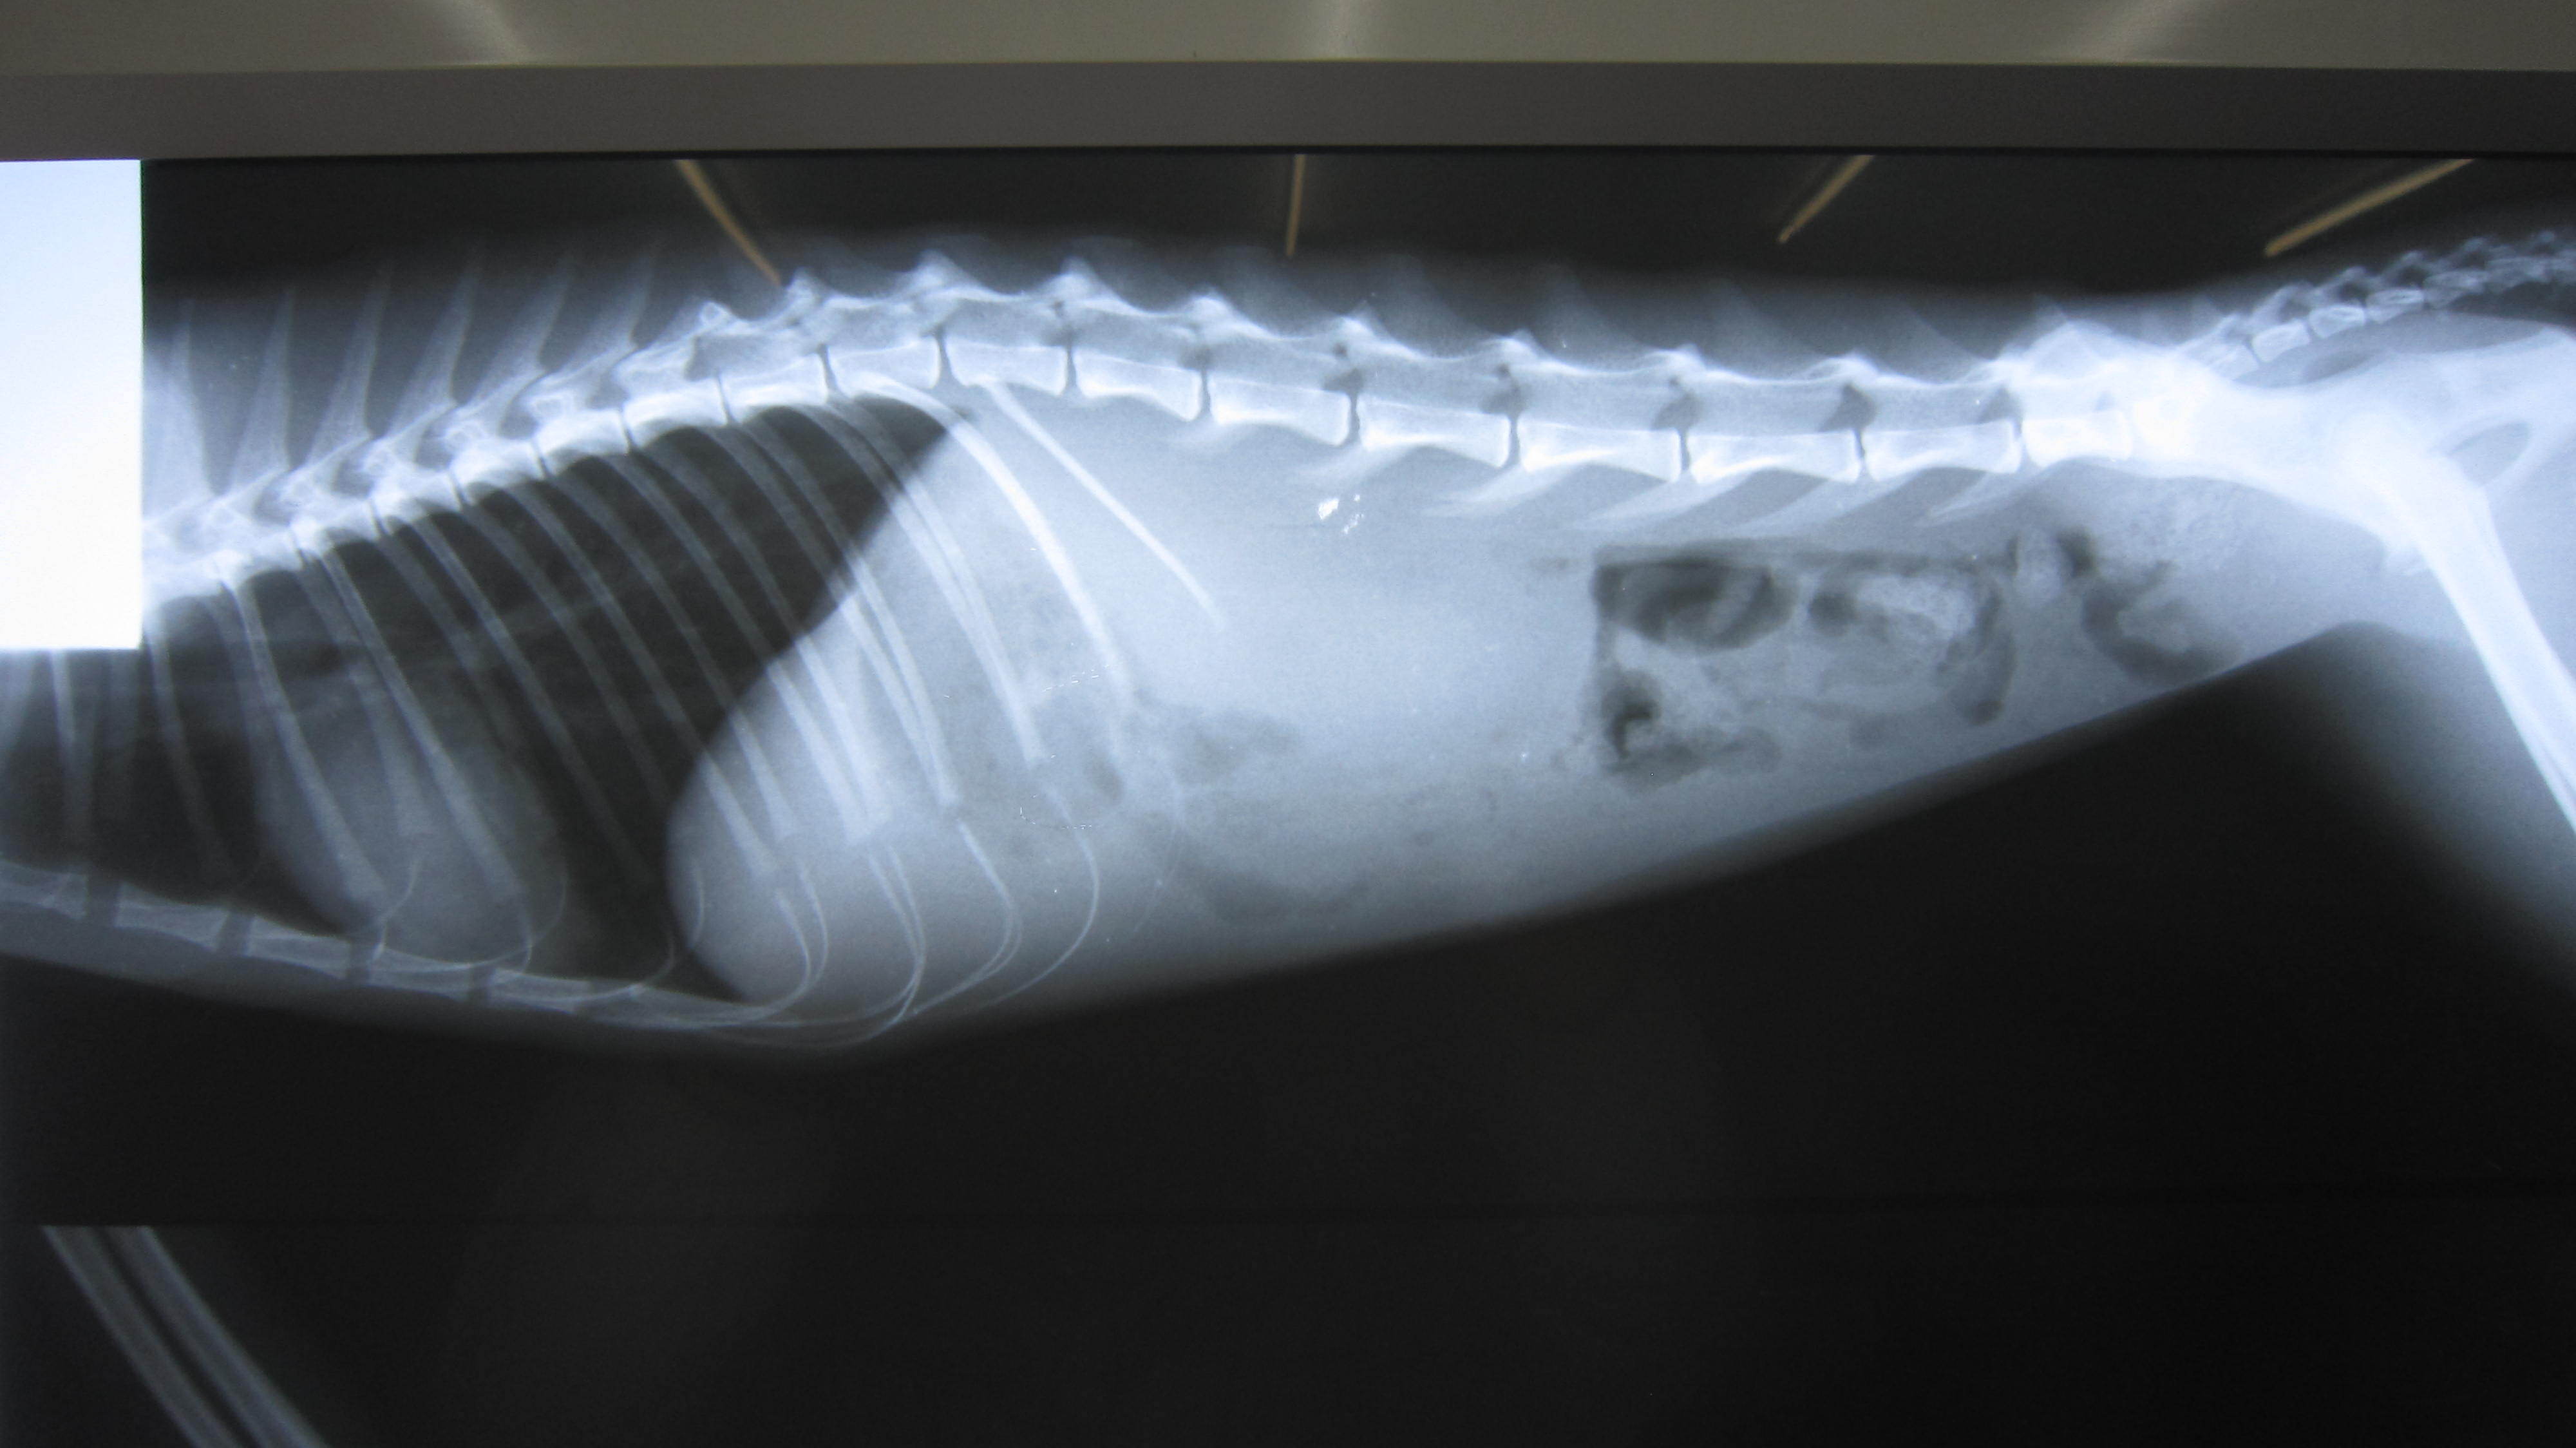

主題: 八德市大湳市場倒在路旁的斷腿貓 申請者姓名: 李明明 花色: 申請日期: 2013-05-14 22:09:32 申請者部落格: 申請者臉書網址: 所在縣市/合作醫院: 桃園縣/綠光動物醫院 治療費用: 4200元 需求人數: 10人 已結案 (2013-06-27 13:14:31) 報名人員: csaoesc x2(已付款)、Tetsu(已付款)、比比(已付款)、蔡釋慧(已付款)、Vavina Kim(已付款)、Sunny Chen(已付款)、Melody Wu x2(已付款)、swatchtw(已付款)、 候補人員: 動物病情說明: 4/26中午接獲市場賣菜阿姨通知:有一隻貓咪斷腿爬行了20多公尺,體力耗盡,倒在路旁待救援,後腿無法站立趴在地上,經通知協會後送往桃園市綠光動物醫院就醫,經X光檢查確定左前肢骨折,脊椎腔挫傷受擠壓導致後腿無法站立,醫生建議先住院以類固醇治療5~7天,觀察脊椎腔受傷及前後肢恢復程度,再決定後續治療方式,因此,初步估計醫療費用約為7千元(無須手術)至5萬元(須手術).由於目前已照顧兩隻受傷/生病浪貓,經濟上無法再行負擔,因此申請協會醫療補助. 動物近況說明: 5/9 PM16:00已由桃園綠動物醫院轉至協會安排的台北光長青動物醫院接手後續治療 (取名:馬太),骨折與韌帶受損部分以限制活動等待受傷部位自然癒合,癒合後也將影響未來的運動能力,會降低競爭力(不適合野放);愛滋/白血 無檢出;血檢有輕微貧血(營養不足)現象;左後腳背傷口須加強清創。(5/12) 有癲癇發作一次,目前繼續觀察中。

左前肢雖骨折但已能稍微站立,恢復情形較佳;後肢因關節韌帶受損、腳背傷口清創&肌肉腫脹,恢復較緩慢。

目前整體恢復情況還算不錯。